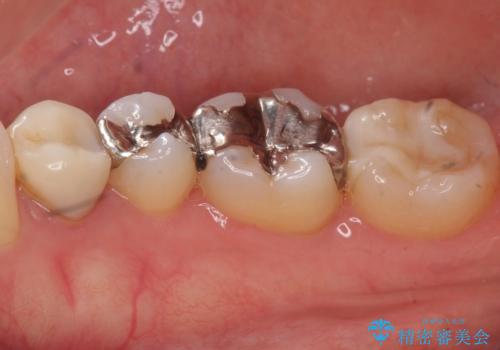

- 口を開けた時、銀の詰め物が目立つとのことで来院。

拡大鏡下で詰め物を外し、う蝕がない事を確認して、セラミック(e-maxインレー)で治療を行いました。

銀の詰め物は歯質との間の隙間ができやすく

虫歯の再発リスクが高いです。